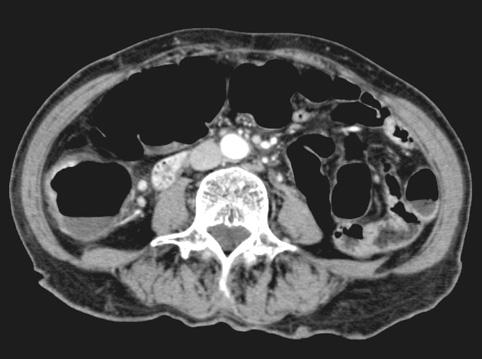

Tuberculosis del Colon que mostró en su esta primaria la semejanza a O-IIc

Enfermedad Inflamatoria - Ulcerativa/Tuberculosis

colon/ascendente

TAC

40 -